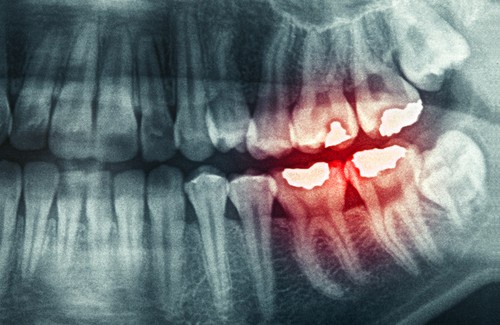

1. Bruxismo

O bruxismo é um problema que afeta mais pessoas do que pensamos. Consiste em apertar os dentes ou rangê-los. Nos casos mais extremos costuma-se utilizar uma placa miorrelaxante. Se não utilizarmos, pode aparecer um desgaste importante nos dentes.

A tensão que se manifesta ao apertar a mandíbula provocará dor de cabeça pela manhã. Isso não é nada mais do que fruto do estresse, das preocupações, da ansiedade ou da depressão. Às vezes, até mesmo o uso de uma placa não evita a dor de cabeça.

O ideal nestes casos não é somente consultar um dentista para que nos passe uma tala que proteja os dentes, como também um psicólogo. É importante saber de onde vem toda a tensão que durante liberamos no ranger dos dentes.